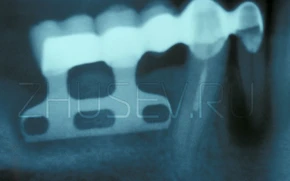

Ручная модификация имплантата фабричного производства.

Пластиночные имплантаты очень часто подпиливали или меняли их конфигурацию непосредственно в момент операции.

Еще один вариант пластиночного имплантата.

Вариантов конструкций имплантатов было просто великое множество. Только тех, которые лично я достал из пациентов, хватило бы на целую брошюру!